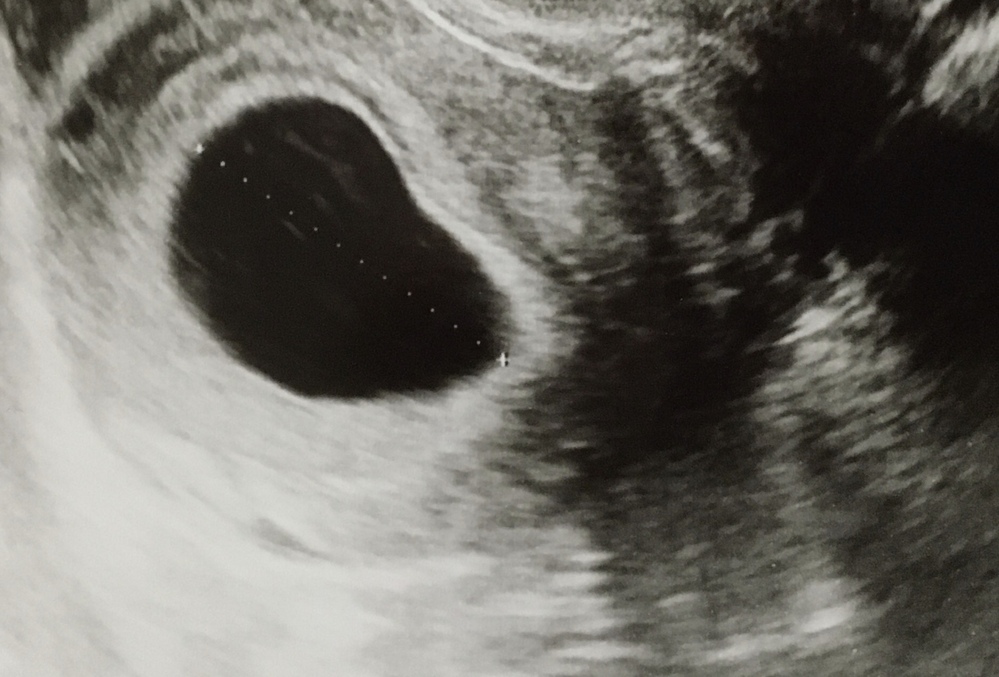

妊娠6週目で胎嚢13mm妊娠8週目にして胎嚢35mmどちらも胎嚢のみ確認 Yahoo 知恵袋

妊娠8週目は、妊娠3ヶ月の第1週目にあたり、妊娠初期と呼ばれる時期です。 お腹の赤ちゃんを「胎児」と呼ぶようになり、検診で「心拍確認できた! 」という方も出てくるでしょう。 また、赤ちゃんの成長と共にママの身体も変化し、一般的につわりがピークを迎える時期とも言われています。 今回は、コズレ会員のみなさんからお寄せいただいた妊娠8 二人目の妊娠時に八週目で稽留流産経験者です。 私は心拍の確認すらできなかったです。胎嚢と胎芽はあるけどそこからは成長なしでした。 その後というのは処置のことですかね? 私はとりあえず自然に出てくるまで少し待ちましょうと言われました。・妊娠8週で胎嚢のみ心拍が確認できず流産しました。 9週目での流産 ・9週で稽留流産でした。 ・繋留流産でした ・心拍確認後でした ・卵管造影の周期初めてのaihでの妊娠でした。 ・染色体異常と判りました ・心拍あっての流産 ・心拍確認後。

妊娠8週4日 8w4d の超音波 エコー 写真

妊娠8週2日 8w2d の超音波 エコー 写真